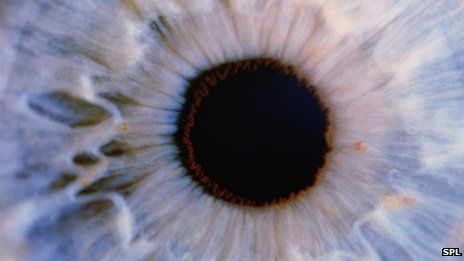

在試驗中,來自牛津大學的研究小組選擇了完全失明的老鼠作為研究對象。這些老鼠的視網膜中完全沒有感光細胞,無法判斷光明和黑暗。

在注入感光細胞后,研究人員不斷觀察這些老鼠能否感受到亮光,檢測在遇到亮光時它們的瞳孔是否會收縮,并用腦部掃描儀觀察老鼠的腦部是否處理視覺信息。結果顯示,接受試驗的老鼠在兩周后視力便有所恢復。